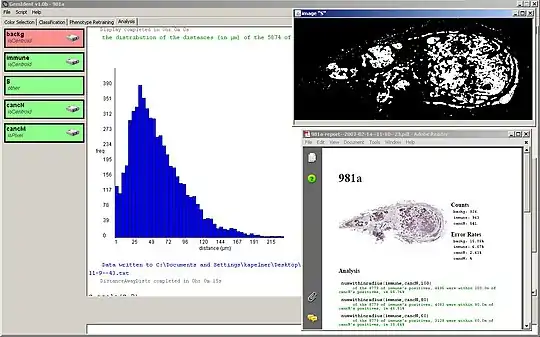

The command-line data analysis and visualization interface in action analyzing results of a classification of a lymph node from the Kohrt study.[2] The histogram displays the distribution of distances from T-cells to neighboring cancer cells. The binary image of cancer membrane is the result of a pixel-only classification. The open PDF document is the autogenerated report of the analysis which includes a thumbnail view of the entire lymph node, counts and Type I error rates for all phenotypes, as well as a transcript of the analyses performed.